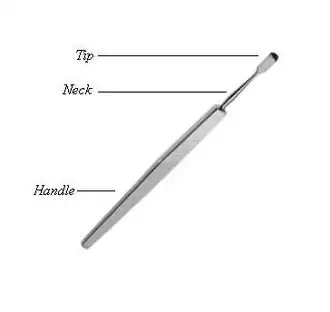

Image gallery

Foreign body spud and needle Cystitome

Cystitome Angular keratotomes